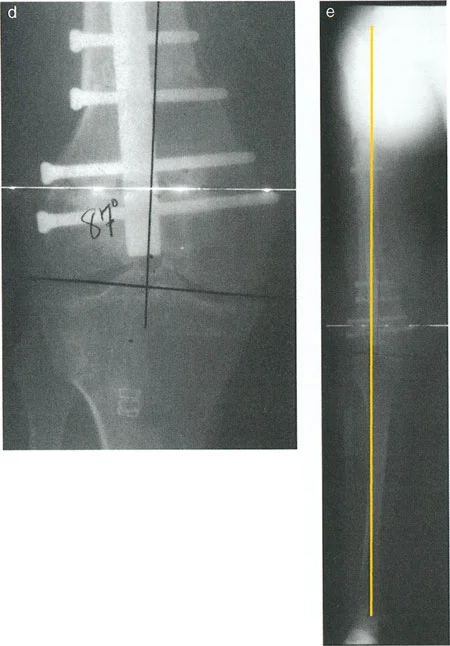

تُعد نقطة إدخال المسمار النخاعي قراراً حاسماً لا يحتمل الخطأ، خاصة في تصحيح التشوهات الصلبة. على عكس الكسور التي قد تسمح ببعض المرونة، فإن تصحيح التشوه يعتمد كلياً على مسار المسمار للحفاظ على المحور الميكانيكي الجديد.

توضح الصورة نقطة البداية الصحيحة للمسمار النخاعي في عظم الساق (الظنبوب) غير المشوه، والتي تقع عادة عند الشوكة الظنبوبية الإنسية.

في عظم الساق (الظنبوب): في الظنبوب غير المشوه، يمر الخط الأوسط للعظم عادة عبر الشوكة الظنبوبية الإنسية. لذلك، فإن نقطة البداية الصحيحة للمسمار النخاعي تكون عادة عند هذه النقطة. ومع ذلك، يختلف التشريح البشري، وقد يمر هذا الخط أحياناً بشكل جانبي أكثر. لذا، من الضروري جداً تخطيط نقطة البداية بناءً على الطرف الآخر السليم للمريض أو التشريح قبل التشوه.

عواقب نقطة البداية الخاطئة:

- جانبية جداً: إذا وُضعت نقطة البداية جانبياً جداً على هضبة الظنبوب، فإن المسمار سيدفع الجزء القريب من العظم إلى تشوه الجنف (Varus).

- إنسية جداً: إذا وُضعت نقطة البداية إنسياً جداً، فإن المسمار سيدفع الجزء القريب من العظم إلى تشوه الفحج (Valgus).

توضح هذه الصورة كيف يمكن أن تؤدي نقطة البداية غير الصحيحة للمسمار النخاعي في عظم الساق إلى تشوهات ثانوية مثل الجنف (Varus) أو الفحج (Valgus) في الجزء القريب من العظم.

يؤكد هذا الواقع الهندسي على مبادئ بالي: يجب أن تتوافق الأدوات الجراحية تماماً مع المحور الميكانيكي المخطط له. أي انحراف بسيط قد يؤدي إلى درجات من سوء المحاذاة في موقع قطع العظم، مما يعرض الإجراء بأكمله للخطر. لهذا السبب، يحرص الأستاذ الدكتور محمد هطيف على التخطيط الدقيق وتنفيذ هذه الخطوات بحرفية عالية.